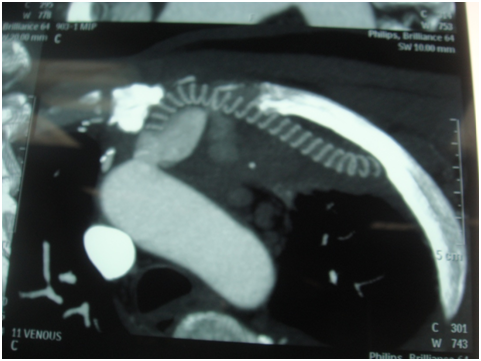

A 55 years old gentleman came to our hospital with discharging chest wound with occasional bleeding through upper chest wound. He was also suffering from fever occasionally. One and half years back he was operated in another hospital with CABG with Aorto-axillary bypass. On 4th postoperative day he needs reopening for mediastinal bleeding and needed a long ICU stay. Then he developed above mentioned symptoms. 5 days back he developed severe bleeding and was treated conservatively in another hospital. After admission CT angiogram was done-showed-Aorto-axillary bypass graft penetrating sternum and developed a leak in the aortic side. We decided for urgent operation on next day on 1.08.13-we went to femoro-femoral bypass first [1].

Figure 2: Aorto-axillary bypass-showing leak and eroding sternum.

Figure 4: Oscillatory saw carefully passed avoiding aneurysmal area eroding sternum.